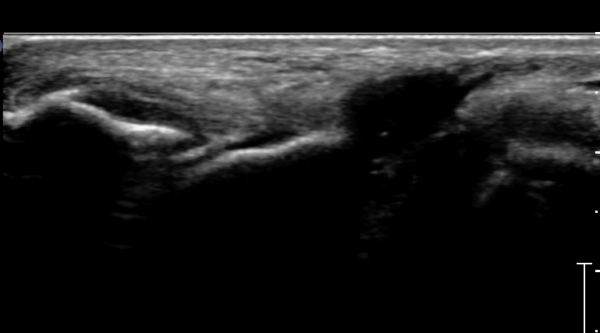

¹ß¸ñ ¿ÜÃø Ⱦ´Ü¸é(ºñ°ñ°Ç Ⱦ´Ü¸é)°Ë»ç¿¡¼­ ºñ°ñ°Ç ½ÉÃþÀÇ ´Ù·®ÀÇ ¼ö¾×Àú·ù°¡ °üÂûµÈ´Ù

(»çÁø 5, 6).